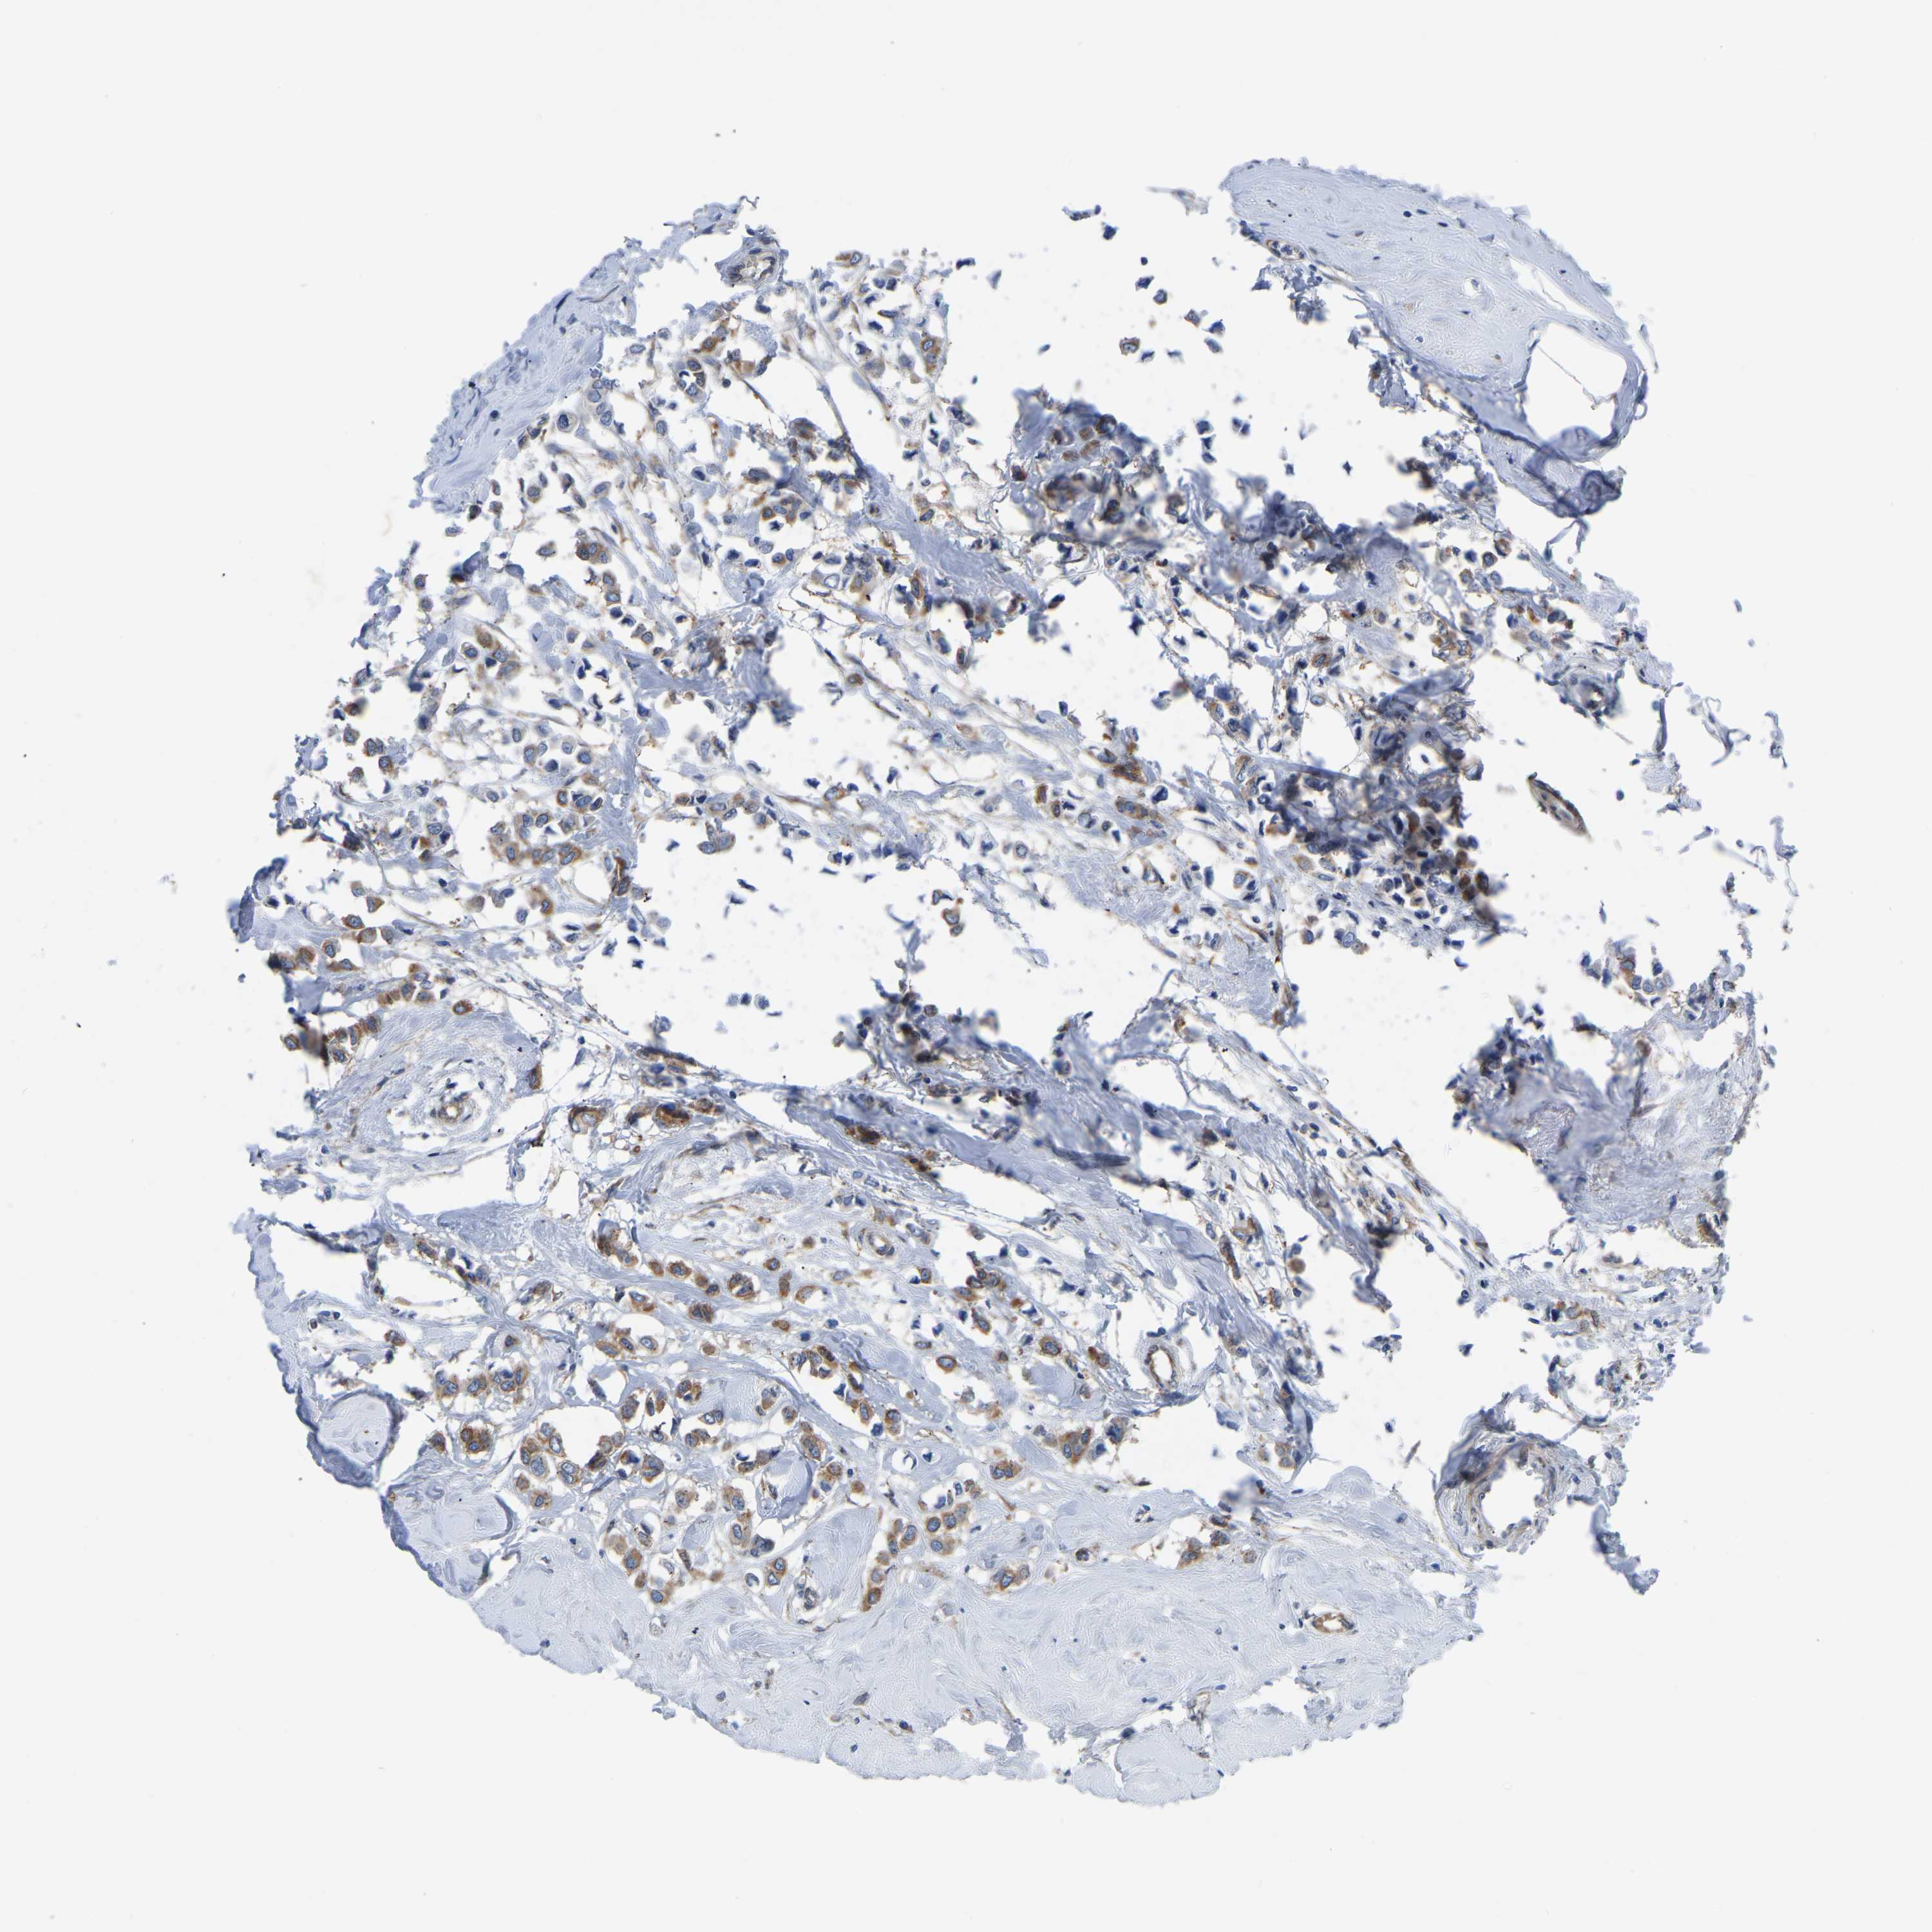

CANCER BREAST CANCER Show tissue menu

BRCA TCGA BRCA VALIDATION PROTEIN EXPRESSION

Breast cancer

Human cancer